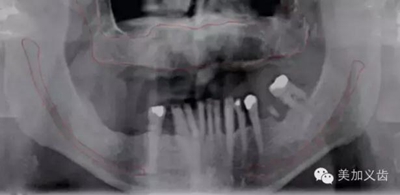

——曲面斷層片

同樣為二維放射線(xiàn)影像,可以獲得如下信息:

·可用骨的高度

·重要解剖結(jié)構(gòu)

·皮質(zhì)骨和松質(zhì)骨的相對(duì)密度

·初篩種植位點(diǎn)病變

其優(yōu)點(diǎn)是:能看到的范圍比根尖片要大很多,尤其是拍攝多牙位時(shí),是根尖片無(wú)法比擬的。設(shè)備成本相對(duì)較低,能開(kāi)展種植的都能買(mǎi)起,放射計(jì)量也比較少。

同時(shí),曲面斷層片也存在缺陷,拍攝后的影像會(huì)有放大,或者存在扭曲和變形,此時(shí)測(cè)量的數(shù)據(jù)是不可靠的。曲面斷層片在拍攝時(shí)存在結(jié)構(gòu)重疊現(xiàn)象,因此會(huì)出現(xiàn)上頜竇粘膜的假陰性和假陽(yáng)性病變,這也是其不準(zhǔn)確的地方。